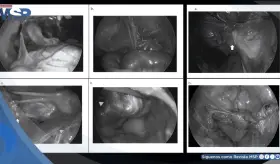

A pesar de los análisis normales, presentaba reserva ovárica baja y hallazgos ecográficos anormales. Durante la cirugía se descubrió daño severo en sus órganos reproductivos, con adherencias, trompas bloqueadas y destrucción del tejido ovárico.